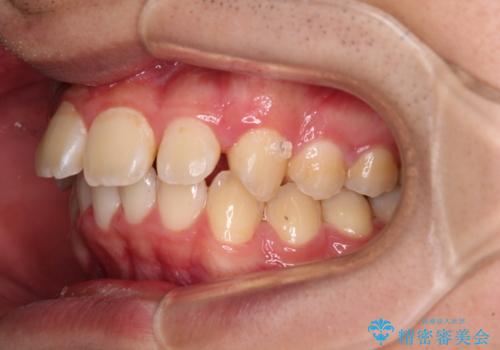

- 深く咬みこんだ前歯と、それに伴い前方に突出した上顎前歯を気にして来院された患者様です。

下顎の歯列は、奥歯が前方に傾斜し、前歯が上顎の歯の付け根に食い込むように内側に傾斜していました。

また、左右の犬歯の位置関係は上顎歯列が前方に位置する咬み合わせとなっており、インビザライン単体で治療するよりは、ワイヤー装置や補助装置を併用した方がより良い仕上がりになることが期待されました。

来院時は学生であったので、補助装置により上顎臼歯を後方に移動させ、下顎歯列はワイヤー装置による傾斜を改善させ、就職のタイミングでインビザラインにて仕上げていくこととしました。

インビザラインで難儀する部分をワイヤー装置にて確実に改善しておくことで、インビザラインのみで行うよりも治療期間を短縮するとともに、より理想的な歯列に近づけて仕上げることができました。